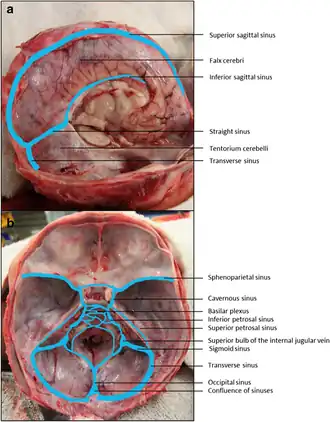

Dural veins

Dural veins -

Major sinuses and their tributaries

Major sinuses and their tributaries